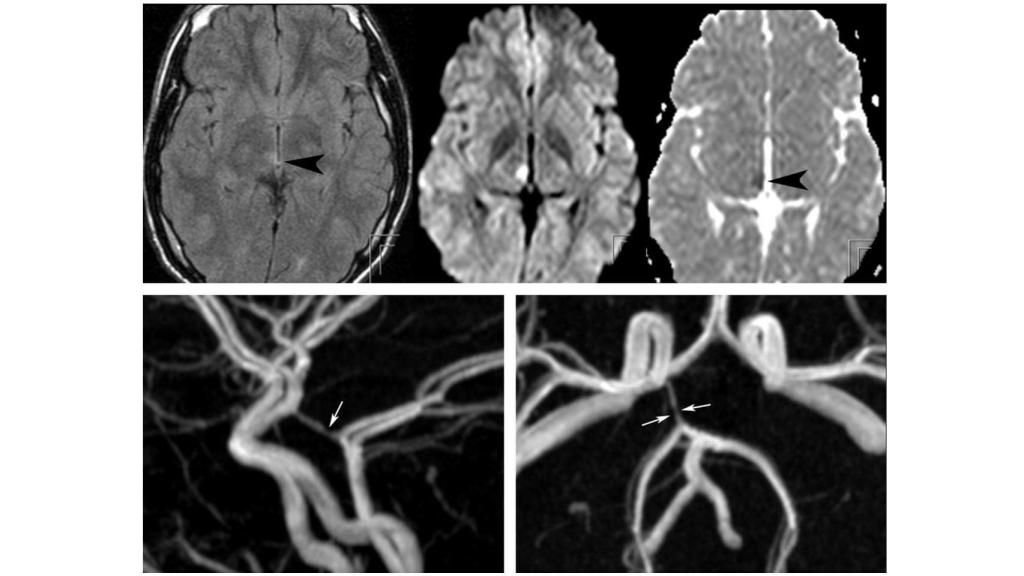

Hemiplejia (parálisis de un lado del cuerpo) por consumo de cocaína. Ajnr.org.